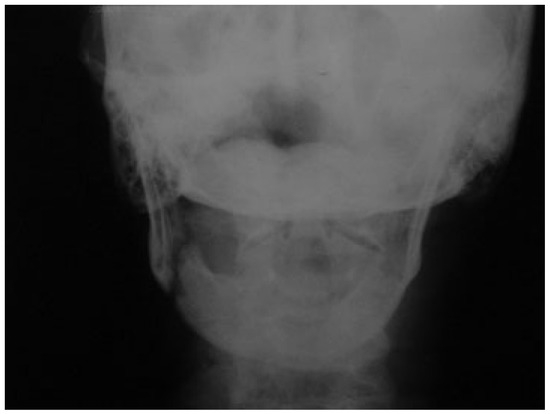

The patient recovered well in the postoperative period, which included use of diabetic and antihypertensive medications besides the usual postoperative medication. The immediate postoperative radiograph showed proper positioning of the segments (Figure 5), and the 2-month panoramic radiography demonstrated that reduction was maintained (Figure 6). The subcondylar fracture was treated with physiotherapy in the postoperative period [15]. The patient has 46 months of follow-up, with 34 mm of mouth opening without functional limitation. The osseous height at the site of the fracture was determined by reassessment [6,9,12], presenting 14 mm at its lowest point and rated as class II according to Luhr et al. [12] classification.

Figure 5. Segments properly positioned in the postoperative posteroanterior mandibular radiograph.